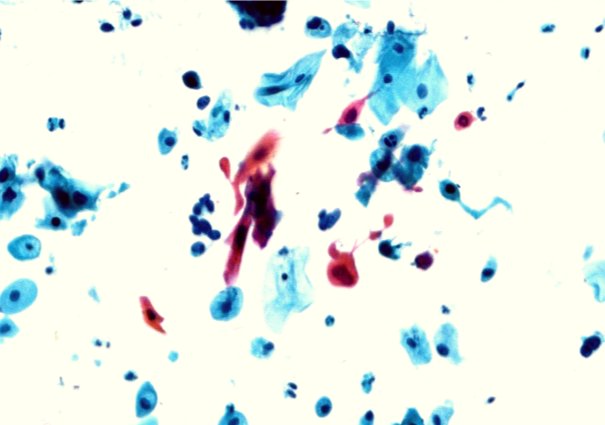

宫颈鳞癌细胞 痰液中的腺癌细胞